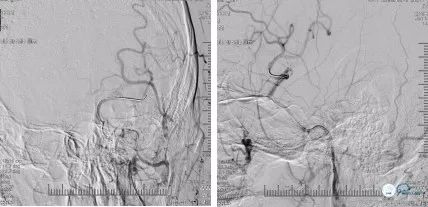

DSA(2018-06-11):右颈内动脉C4-C6段管壁不光滑,多发斑块形成,存在多发串联狭窄;右侧大脑前动脉A1纤细,显影浅淡,右侧大脑中动脉通过软脑膜支向右侧大脑前动脉代偿供血,前交通动脉开放欠佳;左颈内动脉C1段长节段闭塞,局部可见血栓影,左侧颈内动脉C6段以远经眼动脉代偿供血,可见浅淡显影,左侧大脑中动脉、左侧大脑前动脉未见显影;左锁骨下动脉造影可见左侧大脑后动脉通过软脑膜支向左侧大脑中动脉、左侧大脑前动脉代偿供血,左侧后交通未见开放(图5)

在局麻下右股动脉置入8F动脉鞘,沿常规泥鳅导丝携带5F多功能导管、8F球囊导管在路径图下送至左颈内动脉开口处,造影提示:左颈内动脉C1段可见不规则残端,考虑血栓形成可能(图7)

将球囊导管固定于左颈总动脉远端,充盈球囊阻断前向血流(图8)

并反复抽吸多功能导管,抽出一2*3mm致密斑块(图9)

抽瘪球囊,再次多功能导管手推造影:未见明显游离血栓影,仍无明显前向血流(图10)